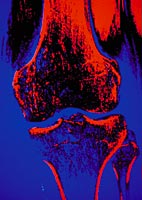

Tearing an ACL is serious business. The ACL¿anterior cruciate ligament¿is the most prominent ligament in the knee, connecting the femur and the tibia. It acts as a rope, holding these important bones together and stabilizing the knee while allowing it to move, extend and twist safely. When the ACL stretches too far, especially in a wrenching motion, it tears. Women are at greater risk for this injury because they have weaker hamstrings (which support the knee) and even because of changes in their menstrual cycle.